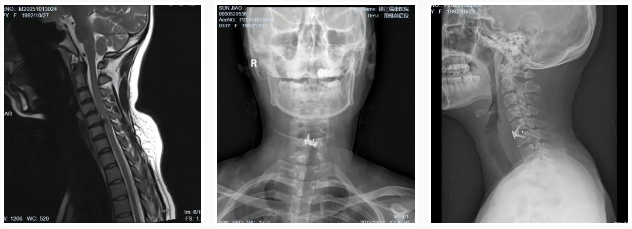

直到最近,情况急转直下。她的左上肢开始出现持续性麻木,手指也变得不灵活,严重影响了工作和生活,甚至夜不能寐。门诊收治入院后,经过详细检查,诊断为“神经根型颈椎病”,这意味着她的颈椎间盘已经严重退化,压迫到了神经。如果不及时治疗,可能会导致肢体瘫痪,后果不堪设想。孙女士最终接受了朱主任团队为其定制的颈椎前路显微镜下椎间盘切除融合术(ACDF),手术很成功,术后她的麻木感和疼痛都得到了明显的缓解 。

孙女士的案例并非个例。长期不正确的姿势,如久坐、低头,会导致颈椎间盘和韧带承受巨大压力,加速其退行性改变。我们发现,许多青少年也因为姿势不当,颈椎生理曲度变直,甚至出现反弓和后突的表现,为日后埋下严重的健康隐患。这些早期退化的迹象,预示着颈椎病正在年轻化,不再是老年人的“专利”。